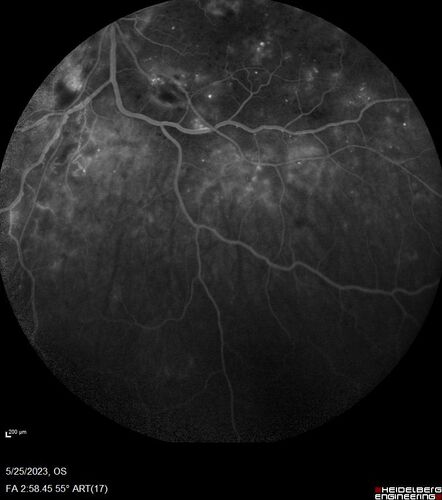

Siegrist Streaks and severe diabetic macular edema

56 year old female who presents four years after developing necrotizing fascitis and multiple organ failure from an infected foot from a roofing nail.  Her vision was 20/100 OU.  She has multiple peripheral pigment spots consistent with Siegrist streaks.